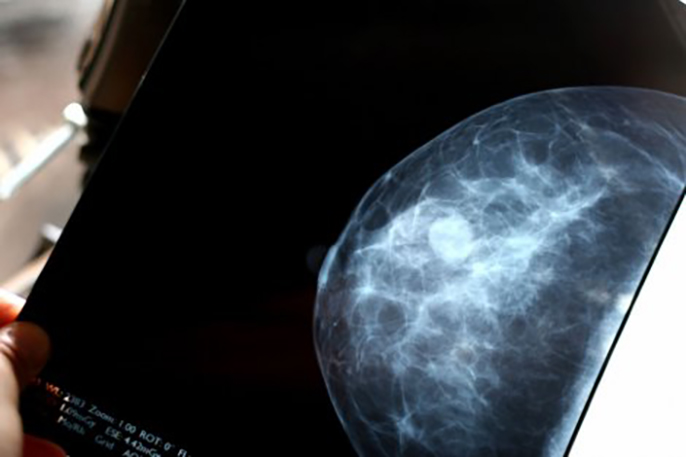

Early-stage breast cancer patients whose tumors carry genetic markers associated with a low risk of disease recurrence may not need to undergo chemotherapy, suggests a new study that employed a test devised by a UC San Francisco researcher.

In the study, reported Aug. 24, in The New England Journal of Medicine, researchers profiled surgically removed tumors from nearly 6,700 patients using a genetic test known as MammaPrint, which predicts the risk of cancer recurrence by measuring the expression of a suite of 70 genes. They found that early-stage breast cancer patients with high “clinical risk” – as determined by conventional measures such as tumor size, the presence of hormone receptors, and metastasis to lymph nodes – but low genetic risk, according to MammaPrint results, had very similar prognoses whether they underwent chemotherapy or not.

Gene expression patterns in tumors differ from individual to individual, and MammaPrint, which is produced by Agendia, a company co-founded by van ’t Veer, represents a new way to assess risk of cancer recurrence in women with breast cancer. The test checks for a 70-gene signature that can predict whether cancer will reoccur in early-stage breast cancer patients.